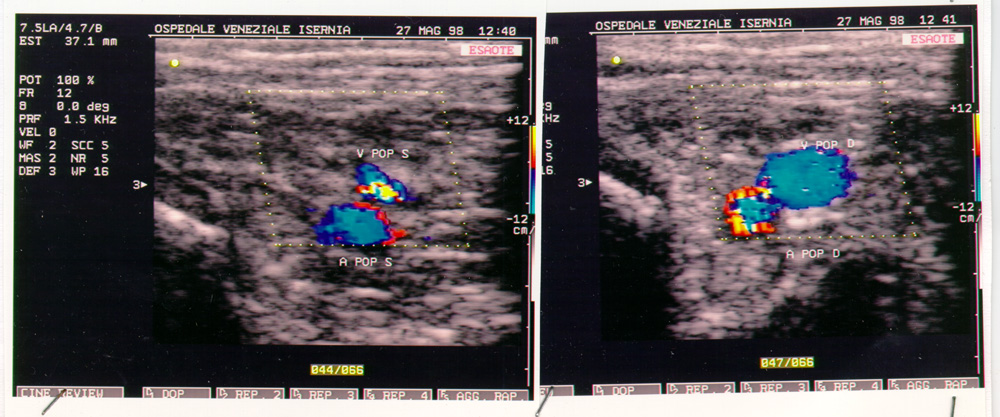

Nel maggio del 98 Maddalena viene ricoverata all'Ospedale di Isernia, per un sospetto virus allo stomaco, la terapia non dà alcun risultato. L'8 luglio viene urgentemente ricoverata all'Ospedale di Agnone. Si scopre un carcinoma invasivo al pancreas. E' colta dalla signora MORTE il 30 agosto 1998 alle cinque ed un quarto del mattino. Il calendario festeggia Santa Tecla. Due giorni dopo invece, se fosse stata in vita, sarebbe ricorso il 47esimo anno di matrimonio. E' morta alla stessa ora in cui era nata. Alle cinque del mattino.